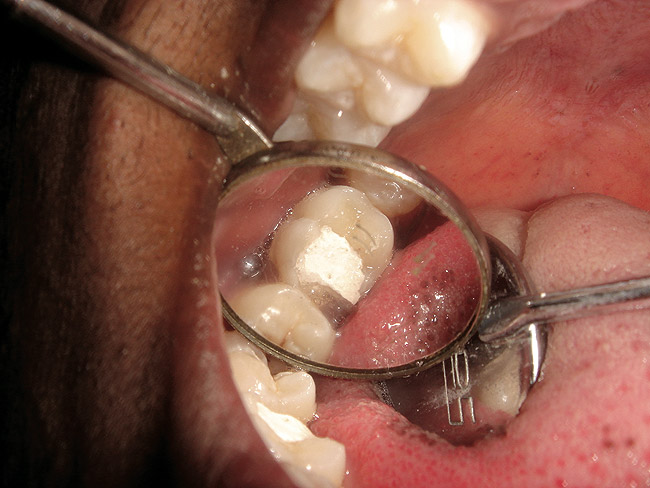

The search for an ideal direct esthetic restorative material is still ongoing. Among the array of RBC materials, some are readily available in the market (flowable, packable, and fiber-reinforced), others have just recently been introduced (siloranes-based), and a few are still in development phase (fluoride-releasing). Individual properties of different RBC materials define their advantages, disadvantages, and clinical uses. Each type of RBC material has its own virtues in some clinical aspects and shortcomings in other aspects. Every material possesses either one or the other ideal properties of a restorative material, but not all of them. Therefore, it is important for a clinician to use every material judiciously and for a clinical application for which it is best suited (Figure 5, Figure 6, Figure 7, Figure 8, Figure 9 and Figure 10).

Figure 5  Clinical applications of RBCs for posterior restorations: occlusal caries restored with silorane-based RBC

Figure 5

Figure 6  Clinical applications of RBCs for posterior restorations: occlusal caries restored with silorane-based RBC

Figure 6